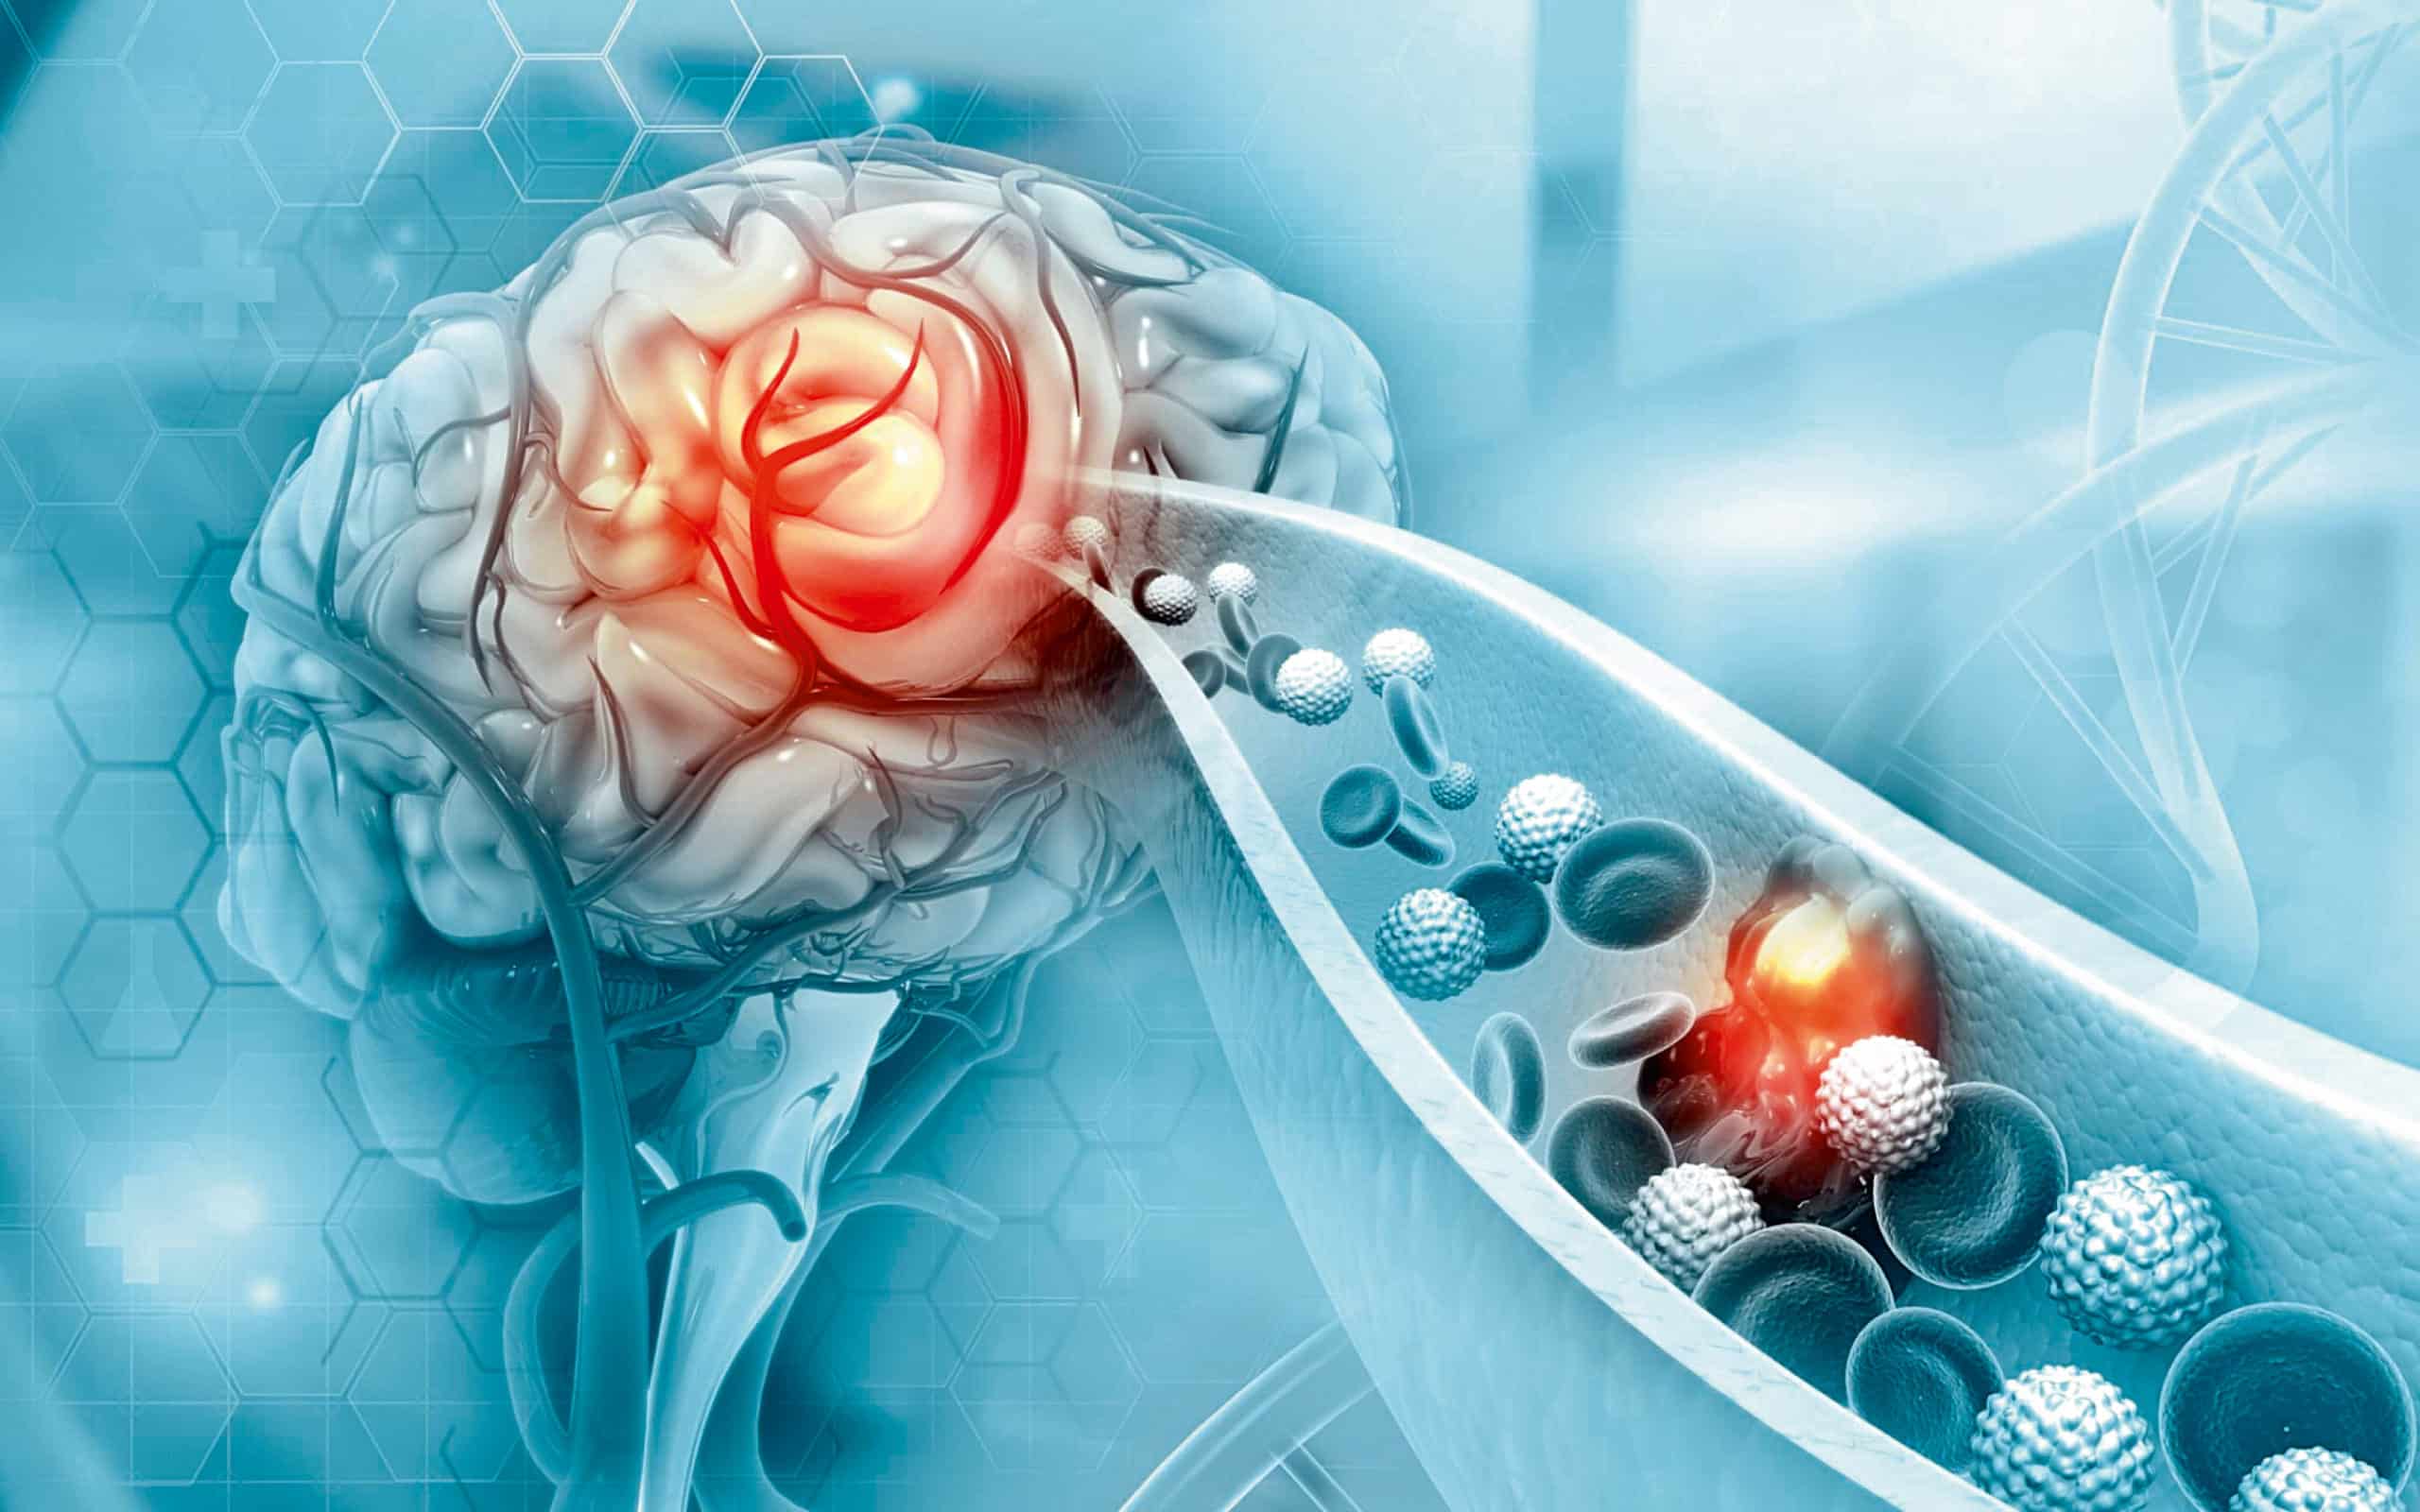

Το εγκεφαλικό είναι μία από τις κύριες αιτίες θανάτου και μακροχρόνιας αναπηρίας παγκοσμίως…

Μπορεί να συμβεί ξαφνικά και χωρίς προειδοποίηση, συχνά με καταστροφικά αποτελέσματα. Ωστόσο, το εγκεφαλικό δεν είναι εντελώς αναπόφευκτο. Με σωστές καθημερινές συνήθειες, ιδιαίτερα γύρω από τα γεύματα και πριν τον ύπνο, ο κίνδυνος μπορεί να μειωθεί σημαντικά.

Το αλκοόλ μπορεί να σας κάνει να νιώθετε υπνηλία αρχικά, αλλά στην πραγματικότητα διαταράσσει την ποιότητα του ύπνου και μπορεί να αυξήσει την πίεση κατά τη διάρκεια της νύχτας. Η χρόνια κατανάλωση καταστρέφει τα αγγεία, αυξάνει τον κίνδυνο κολπικής μαρμαρυγής (κύρια αιτία εγκεφαλικού) και αποδυναμώνει την ικανότητα του εγκεφάλου να ανακάμψει από μικροτραυματισμούς.